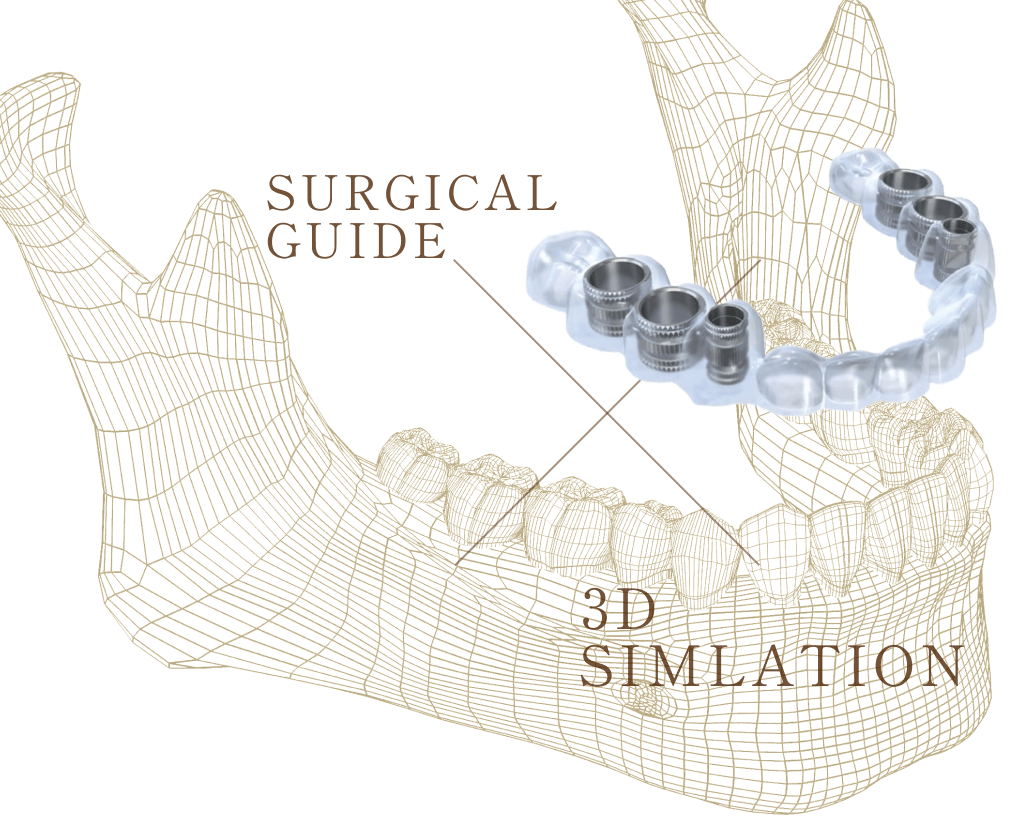

当院はインプラント治療の成功率を向上させるために、歯科用CTを導入しています。CTを使うことで患部を立体的に撮影でき、骨の状態、神経や血管の位置を詳細に把握できるため、インプラント埋入位置の決定や、骨造成が必要かどうかなどの判断が可能になります。

インプラント埋入位置の決定や、骨造成が必要かどうかなどの判断が可能になります。

治療精度を高めるサージカルガイド

当院は安全なインプラント手術のために「サージカルガイド」を使用しています。これは患者様のお口に合わせて作製されるマウスピース型の装置で、インプラントを埋入する正確な位置・深さ・角度が設定されています。

手術中のミスを防ぐだけでなく、歯肉を切開せずにインプラント埋入ができるため、術後の痛みや出血などを抑えられます。当院は正確かつ低侵襲なインプラント治療を目指しています。